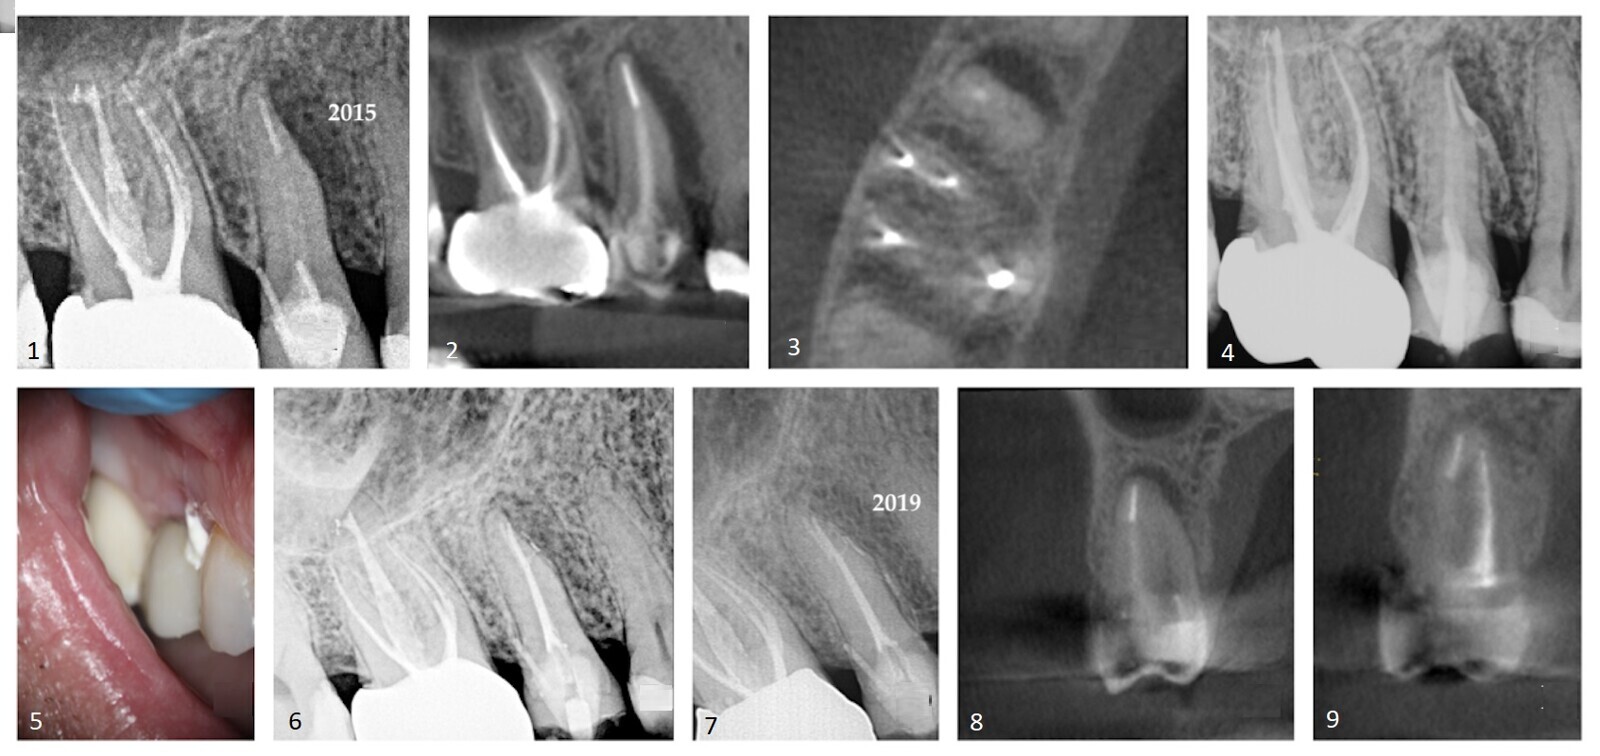

Le patient a fourni une radiographie périapicale montrant une radioclarté périradiculaire mésio-proximale associée à la dent #15 (Fig. 1). La coupe sagittale du volume CBCT (Carestream CS 9000, Carestream Dental) montrait l'étendue de la lésion (Fig. 2). Dans la précédente thérapie radiculaire, seul le canal buccal avait été détecté et traité. La coupe axiale montrait un canal palatin non traité (Fig. 3) . Un tenon fibré placé dans le canal buccal avait été utilisé pour retenir le noyau. Le patient a été informé que la broche d'ancrage mal orientée s'étendait dans le ligament parodontal. Avec l'accord du patient, il a été décidé de traiter sélectivement le canal palatin.

Après une période intermédiaire de traitement à l'hydroxyde de calcium de six semaines (UltraCal XS, Ultradent ; Figs. 4 & 5), 6 l'espace canalaire a été obturé à l'aide d'une technique de condensation verticale chaude. 7 Le matériel d'obturation a été exprimé dans une porte de sortie ramifiée latérale (Fig. 6). Le suivi de quatre ans a montré une résolution de la lésion latérale (Figs. 7–9). La présomption initiale d'une racine fracturée s'est avérée fausse, ce qui suggère que le diagnostic d'affections basé sur une acquisition de données insuffisante n'est pas fiable. L'utilisation du CBCT est un impératif dans les procédures endodontiques de toute nature, à condition que les principes ALARA (aussi bas que raisonnablement réalisable) concernant la dose de rayonnement soient suivis.

Cas 1—Fig. 1 : Une zone de raréfaction périradiculaire était évidente le long de la face mésio-proximale de la dent #15. Un traitement antérieur du canal radiculaire et un tenon et un noyau retenus par une broche supportant une couronne en zircone ont été notés. Fig. 2 : La coupe sagittale du volume CBCT montrait la lésion latérale s'étendant jusqu'à la crête alvéolaire. Fig. 3 : La coupe axiale du volume CBCT montre l'étendue de la raréfaction adjacente à la face mésiale de la racine et la présence d'un canal palatin non traité. Fig. 4 : Un traitement sélectif du canal palatin a été réalisé. De l'hydroxyde de calcium a été inséré dans l'espace canalaire. Fig. 5 : L'extrusion du médicament provisoire à base d'hydroxyde de calcium à travers la zone sulculaire de la dent n° 15 était évidente. Fig. 6 : Une branche latérale de l'espace canalaire contenant le matériau d'obturation sortait dans l'interface des tiers moyen et apical de la racine. Fig. 7 : Une radiographie périapicale prise quatre ans après le traitement a montré une régénération osseuse et la reformation du ligament parodontal. Fig. 8 : La coupe coronale du volume CBCT montrait la radiotransparence périradiculaire préopératoire. Fig. 9 : La coupe coronale du volume CBCT prise quatre ans après le traitement a montré la résolution de la radiotransparence périradiculaire.